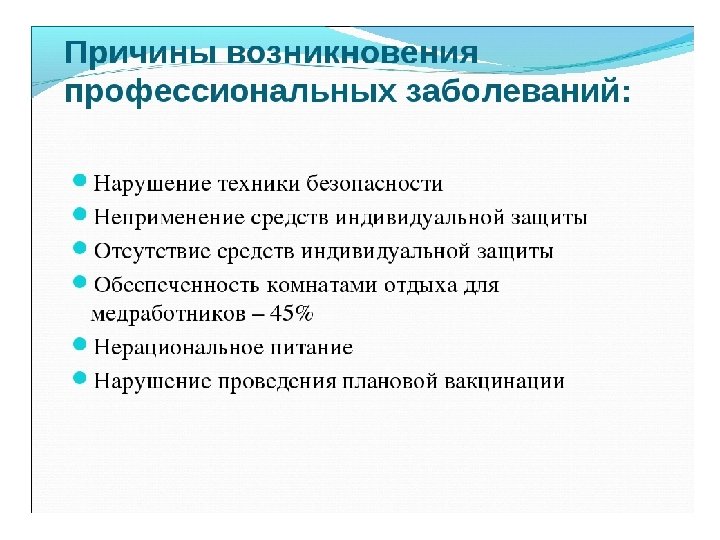

Самостоятельная работа (интерактив). Составление программ по управлению факторами риска развития профессиональной патологии. В роли эксперта специалиста по медицине труда выступает группа обучающихся. 2 Кейса: 1. Программа по управлению профессиональными факторами риска офиса (банковские служащие) 2. Программа по управлению факторами риска в клинической научно исследовательской лаборатории (химические реактивы, биологические жидкости, подопытные животные, микроскопия.